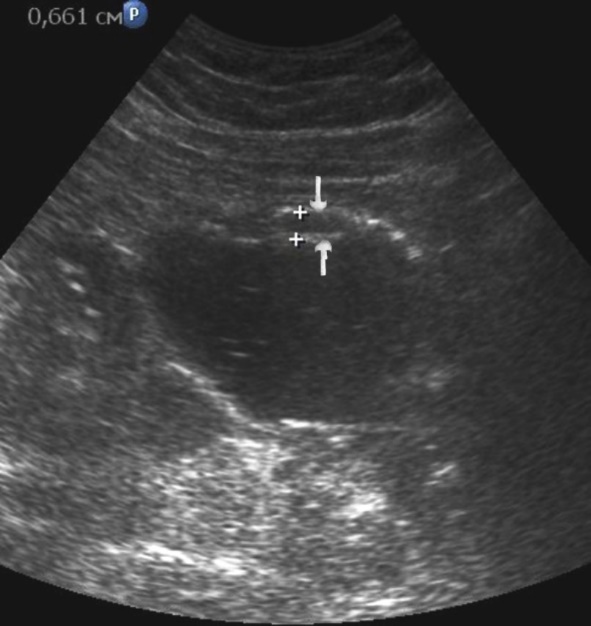

Distal gastric cancer was observed in 24 (39,3%) cases and contributed to the development of pyloric stenosis: in 6 (9,8%) cases it was compensated, in 18 (29,5%) – was sub compensated. The layers of the wall were not differentiated in all patients with sub compensated pyloric stenosis. In the case of compensated pyloric stenosis, the thickness of the affected area was 10,2±2,9mm, the length was 27,1±6,2mm, the diameter of the pylorus was 8,3±0,8mm (Figure 14). Among patients with sub compensated pyloric stenosis, the thickness of the stomach wall was 19,8±4,1mm, the length was 43,6±4,5mm, the pyloric diameter was 4,3±1,1mm (Figure 15).

Figure 15.Distal gastric carcinomas of diffuse infiltrative form of T3 stage. Sub compensated pyloric stenos (arrows). The thickness of the anterior wall of the stomach is 9,13 mm, extent of the affected area – 7,84 cm. On an empty stomach in the cavity of the stomach is determined an a large amount of fluid. The diameter of the pyloric canal is about 6 mm.